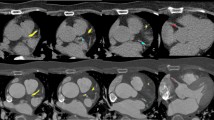

The distribution of calcium along the aorta is usually very heterogeneous. It is possible to identify coarse calcium in one segment, while there is no calcium in another segment from the same individual, as shown in Fig. 1. In the first case (images 1a and 1b), there was calcium in large amount in the arch and descending thoracic segments, while there was no calcium in the ascending aorta. In the second case (images 1c and 1d), the calcium concentration was much higher in the aortic arch compared with ascending and descending thoracic portions.

Heterogeneous distribution of calcium along the aorta. a, b CT reconstructions in the parasagittal plane. In this case, ascending aorta had no calcium (arrow in a), whereas in the arch and descending portions (arrow in b) there were circumferential plaques covering almost all aortic wall. c, d CT reconstructions in the axial plane. The most calcium concentration was in the aortic arch (arrow in c), while in ascending (superior arrow in d) and descending (inferior arrow in d) segments calcium were coarse, but sparse

The variation in the distribution of calcium across aorta segments may be in part associated with different embryonic origin of the vascular smooth muscle cells colonizing the aorta, which in the aortic arch derives from cardiac neural crest cells, whereas the calcium found in the descending aorta derives from the mesoderm [16]. The Leroux-Berger et al. study found correlation between the embryonic origin of vascular smooth muscle cells and the timing of the appearance of calcium [16]. Thus each aortic segment differs in their embryonic origin and is subject to different hemodynamic stress, which also appears to affect susceptibility to calcium [16], as the rate of calcium seems to differ among individuals [17]. Therefore, the calcium found in each aortic segment may be associated differently to cardiovascular risk factors [18] and probably has distinct predictive value for cardiovascular (CV) and non-CV morbidity and mortality, as suggested in some studies [12, 13, 19, 20•, 21•].